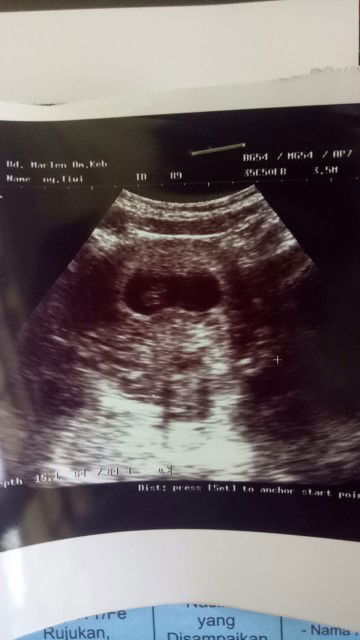

Alhamdulillah udh kelihatan janin nya,,